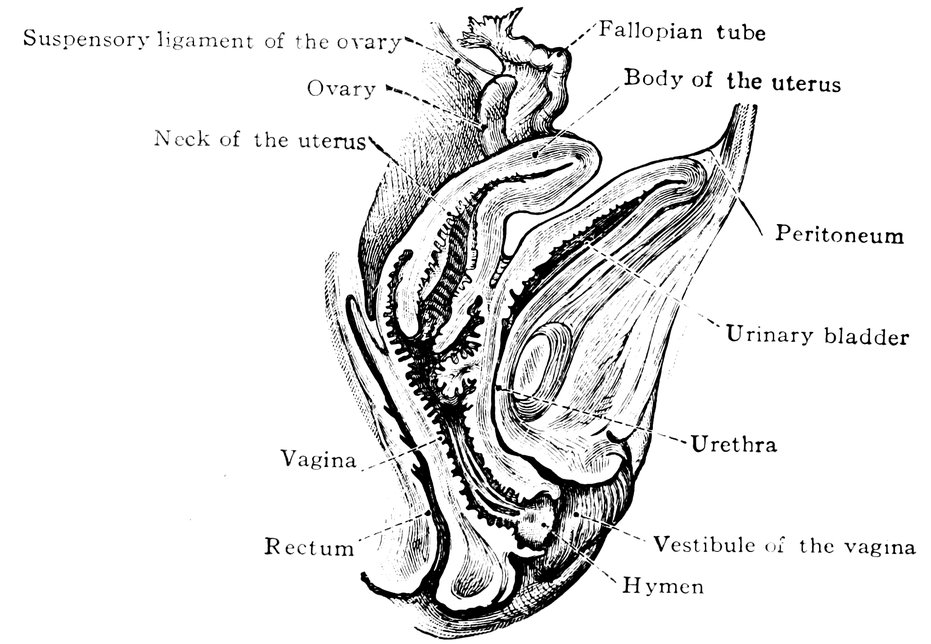

| 2. | Portion of the pelvic viscera in the female, etc. | 9 |

| 14. | Sagittal section of the female pelvis | 56 |

Fig. 2.—Portion of the pelvic viscera in the female, and their relation to the muscles of the pelvic outlet (or perineal muscles), shown in the left half of the pelvis, seen from the right side.—The parametrium. (From Toldt: Atlas of Human Anatomy.—Rebman Company, New York.)